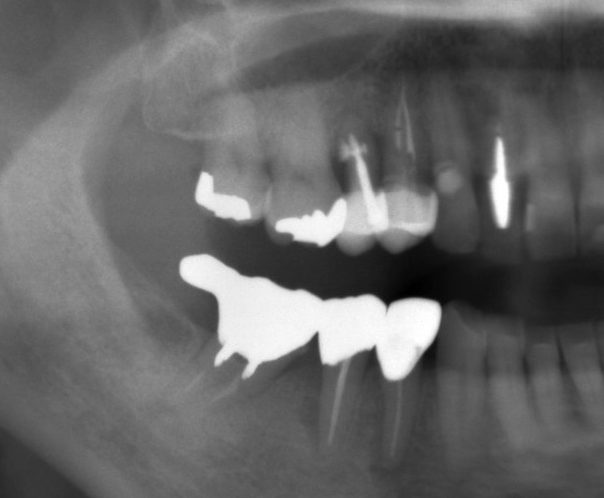

インプラントを行った部位の歯は、神経の処置がしてあり、痛みはありませんでしが、2次虫歯が酷く、また骨(歯槽骨)が破壊されており、残念ながら抜歯を行いました。

骨の状態も悪く、そのままではインプラントが埋入できなかったので、GBR(骨を造る処置)を行って埋入しています。

インプラントの手前の歯は、根管治療を行いセラミックの被せ物をしました。

奥の歯2本は、それぞれ2次虫歯でしたが、神経は感染していなかったので、健康なエナメル質は温存して、セラミックとジルコニアで治療を行いました。